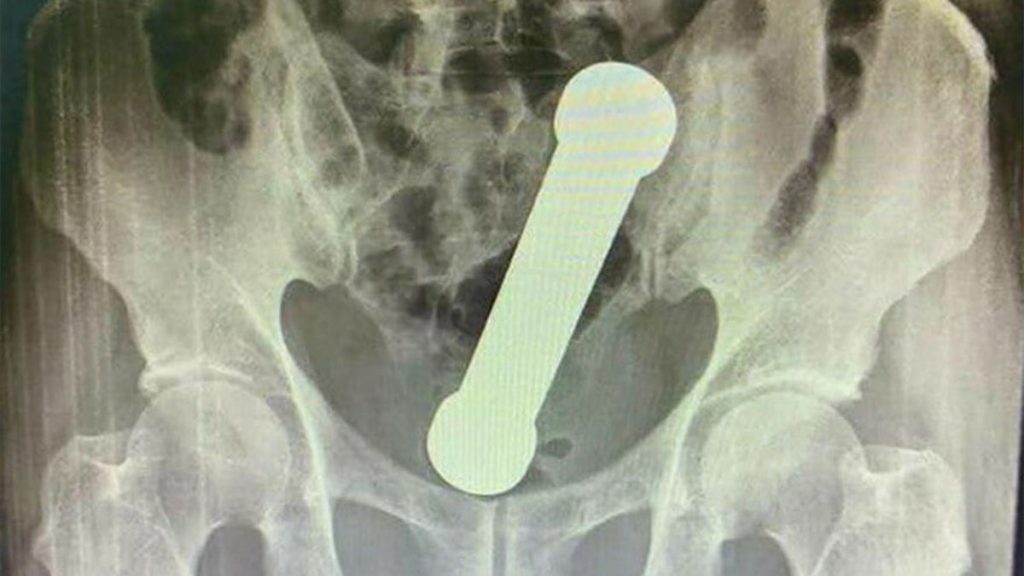

Radiografías mostraron la pesa entre el colon y el recto

Esta es una de las radiografías realizadas al paciente, publicada por la misma revista científica: